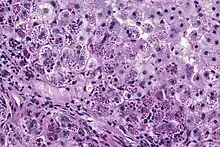

With A1AT deficiency, the pathogenesis of the lung disease is different from that of the liver disease, which is caused by the accumulation of abnormal A1AT proteins in the liver, resulting in liver damage.[9] As such, lung disease and liver disease of A1AT deficiency appear unrelated, and the presence of one does not appear to predict the presence of the other.[9] Between 10 and 15% of people with the PiZZ genotype will develop liver fibrosis or liver cirrhosis, because the A1AT is not secreted properly and therefore accumulates in the liver.[18] The mutant Z form of A1AT protein undergoes inefficient protein folding (a physical process where a protein chain achieves its final conformation). 85 percent of the mutant Z form are unable to be secreted and remain in the hepatocyte.[9] Nearly all liver disease caused by A1AT is due to the PiZZ genotype, although other genotypes involving different combinations of mutated alleles (compound heterozygotes) may also result in liver disease.[9] A liver biopsy in such cases will reveal PAS-positive, diastase-resistant inclusions within hepatocytes.[9] Unlike glycogen and other mucins which are diastase sensitive (i.e., diastase treatment disables PAS staining), A1AT deficient hepatocytes will stain with PAS even after diastase treatment - a state thus referred to as "diastase resistant". The accumulation of these inclusions or globules is the main cause of liver injury in A1AT deficiency. However, not all individuals with PiZZ genotype develop liver disease (incomplete penetrance), despite the presence of accumulated mutated protein in the liver.[9] Therefore, additional factors (environmental, genetic, etc.) likely influence whether liver disease develops.[9]

The gold standard of diagnosis for A1AD consists of blood tests to determine the phenotype of the AAT protein or genotype analysis of DNA.[9] Liver biopsy is the gold standard for determining the extent of hepatic fibrosis and assessing for the presence of cirrhosis.[9]